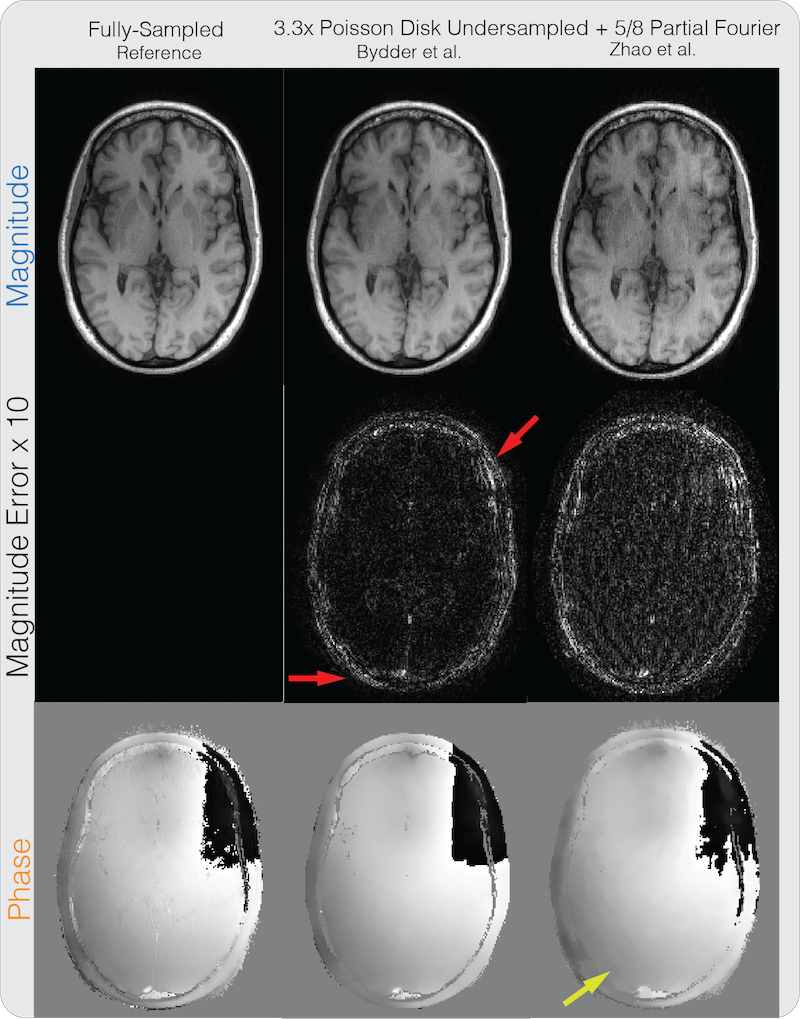

A partial Fourier factor of was retrospectively applied on both datasets. The brain dataset was further retrospectively under-sampled by with variable density Poisson-disk pattern and a calibration region. The proposed method with and without phase cycling were applied on the under-sampled datasets and compared. regularization was imposed on the Daubechies 6 wavelet domain for the phase image. The homodyne method from Bydder et al. [17] with regularization on the wavelet domain was applied and compared. The method was chosen for comparison because it was shown to be robust to errors in the phase estimate as it penalizes the imaginary component instead of enforcing the image to be strictly real. The original formulation included only regularization on the real and imaginary components separately. To enable a fair comparison using similar image sparsity models, we modified the method to impose wavelet regularization on the real and imaginary components separately to exploit wavelet sparsity, which achieved strictly smaller mean squared error than the original method. The number of iterations was set to be 1000. The regularization parameters were set similarly to how the magnitude and phase regularization parameters were selected.

Figure 5 shows the partial Fourier reconstruction results combined with PI and CS on the brain dataset with the proposed method. The figure compares the proposed reconstruction with and without phase cycling. Again, without phase cycling, significant artifacts can be seen in the magnitude image near phase wraps in the initial solution, pointed by the yellow arrow. Reconstruction with phase cycling does not display these artifacts. Figure 6 shows the results for the method of Bydder et al. and Zhao et al. As pointed out by the red arrows, the method of Bydder et al. shows higher error in the magnitude image compared to proposed method with phase cycling in these regions. The method of Zhao et al. shows higher magnitude image error in general, and displays staircase artifacts in the phase image, which are common in total variation regularized images, as pointed by the yellow arrow. In terms of PSNR, the method of Bydder et al. resulted in 33.64 dB, the method of Zhao et al. resulted in 30.62 dB, the proposed method without phase cycling resulted in 30.35 dB, and the proposed method with phase cycling resulted in 34.91 dB. One instance of our Matlab implementation of the proposed method took 1 minute and 53 seconds. We note that the severity of the artifact in the reconstruction without phase cycling for the brain dataset is much stronger than for the knee dataset because a higher regularization was needed to obtain lower reconstruction mean squared error. This is because the brain dataset was further under-sampled for CS. Larger regularization led to larger thresholding errors around the phase wraps and hence more significant artifacts in the resulting reconstructed images.

One advantage of our proposed method is that more appropriate phase regularization can be enforced for each application. In particular, we compared our proposed method with the methods of Bydder et al., and Zhao et al. for partial Fourier imaging. The method of Bydder et al. requires imposing regularization on the image imaginary component, which does not necessarily correlate with regularization of the phase image. The method of Zhao et al., on the other hand, only supports finite difference penalties, which can result in staircase artifacts, shown in Figure 6. Our proposed method can impose a more general class of phase regularization, and in the case of partial Fourier imaging, the proposed method with Daubechies-6 wavelet sparsity constraint on the phase image resulted in the highest PSNR among the compared methods. For water-fat imaging, we compared our proposed method with the method of Sharma et al., and achieved similar image quality for both fully-sampled and under-sampled datasets. With phase cycling, our proposed method can be extended to include partial Fourier imaging in a straightforward way. Since the method of Sharma et al. solves for the absolute phase, it is unclear whether their proposed restricted subspace model can be extended to enforce smoothness of water and fat phase images, which often contain phase wraps, and more effort is needed to investigate such extension. Finally, through comparing the proposed method on divergence-free flow imaging and -ESPIRiT with divergence-free wavelet denoising, we have shown the advantage of joint PI + CS reconstruction utilizing phase structure over separate application of PI + CS reconstruction followed by phase image denoising.

6.

Partial Fourier + PI + CS reconstruction comparison results on the same brain dataset in Figure 5. The method of Bydder shows higher error in the magnitude image compared to proposed method with phase cycling in regions pointed out by the red arrows. The method of Zhao et al. shows higher magnitude image error in general, and displays staircase artifacts in the phase image, which are common in total variation regularized images, as pointed by the yellow arrow.